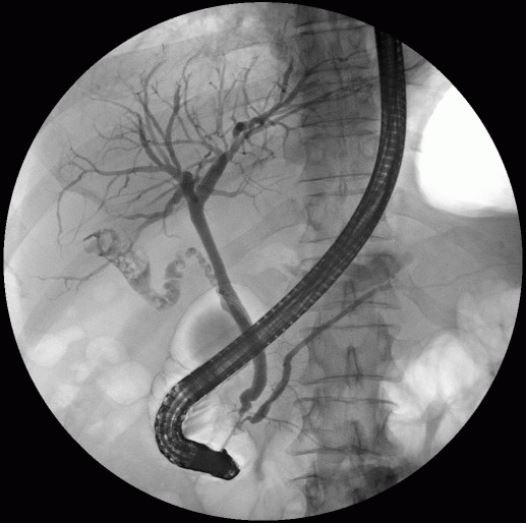

ERCP

- 내시경적역행담췌관조영술 이라고 부르며, 총담관에 삽입한 내시경을 통해 담도계 및 췌관에 조영제를

주입하여 X선 촬영을 하는 검사입니다.

조직검사도 가능하지만 폐쇄성황달, 담도폐쇄 등 스텐트 삽입 시술시 췌담관의 병변을 동시에 볼 수 있어

일반적으로 병세가 심한 환자들을 대상으로 합니다.

그렇기때문에 입원하여 정밀검사를 받는 것이 원칙이며 EUS FNA와 마찬가지로 검사전 금식이 있습니다.

합병증이나 부작용이 동반될 수 있기때문에 외래로는 검사할 수 없습니다.